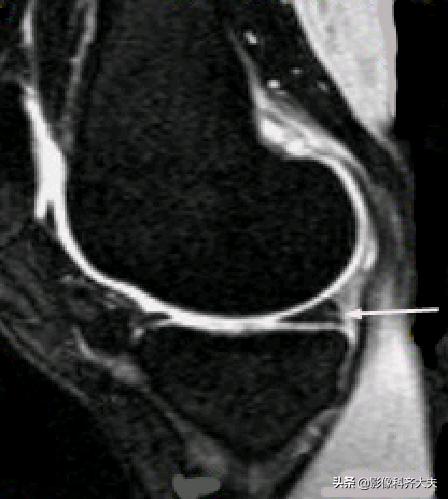

腘肌腱腱鞘: